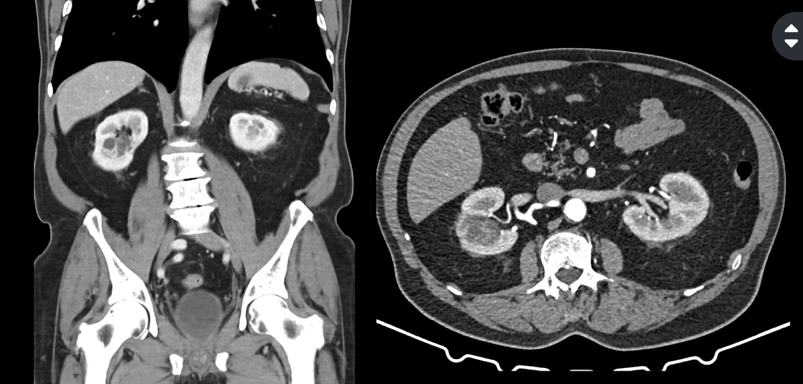

En Hospital CIMA Hermosillo, integramos nuestro Neuro EcoSistema con tecnología de última generación que mejora la precisión y seguridad en tu cirugía de columna o neurocirugía, reduciendo riegos con el soporte de imágenes en tiempo real y reduciendo tu exposición a la radiación.